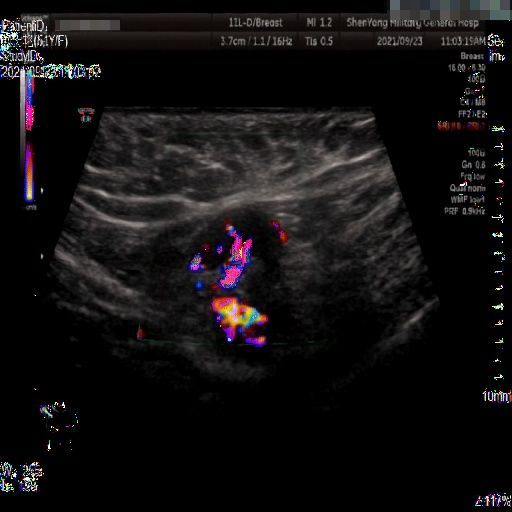

Images with certain annotations are considered noisy images in the context of the noise removal task, and corresponding images without these annotations are considered clean. Some typical images with various annotation are provided in Fig. 1.

The vascular flow annotation is not an additional labeling feature meant to simplify identification. Rather, it serves as a bounding box that identifies the specific area of the image being examined by the ultrasound flowmeter. However, to keep things simple, we will continue to call it a form of annotation. The presence of this annotation indicates that the relevant examination has been conducted.

(b)

Figure 1: Images with various annotations. (a) body marker annotation, (b) radical line annotation, (c) vascular flow annotation.